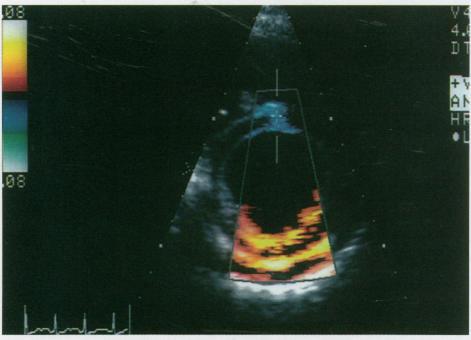

Advances in ultrasound technology will continue to expand the utility of echocardiography in the assessment of structural and functional cardiac disease in children. Tissue Doppler imaging and dobutamine stress echocardiography are 2 promising clinical applications that are expected to become increasingly used with time. Advances in data compression technology, including JPEG and MPEG techniques, will significantly affect digital archival and transmission of echocardiograms, which also have clinical implications, particularly in the expanding use of telemedicine. Continued research and clinical experience will further define the ultimate roles of these technologies in the future.

超声技术的进步将继续扩大超声心动图在评估儿童心脏结构和功能疾病方面的应用。组织多普勒成像和多巴酚丁胺负荷超声心动图是两项很有前景的临床应用,预计随着时间的推移会越来越多地被使用。包括JPEG和MPEG技术在内的数据压缩技术的进步,将显著影响超声心动图的数字存档和传输,这也具有临床意义,特别是在远程医疗日益广泛的应用中。持续的研究和临床经验将进一步明确这些技术在未来的最终作用。